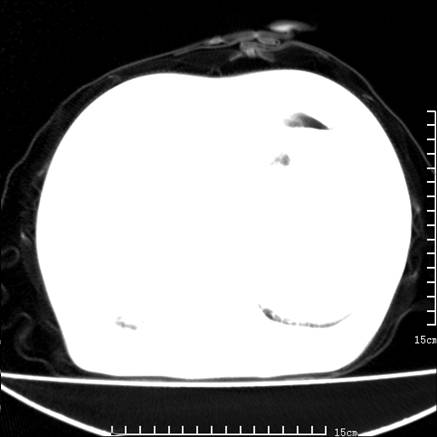

女,王某,58岁,咳嗽三个月余,基层医院二个月前诊为肺结核,用抗结核药二个月无明显疗效。

心包积液致肺瘀血.右侧周围型肺癌伴肺内转移,中间裂积液,叶间胸膜肥厚.右上肺大泡,右侧胸膜肥厚.

双肺继发型tb,心功能不全并肺淤血、心包、双侧叶间裂积液,肺大泡,右下胸膜肥厚钙化。